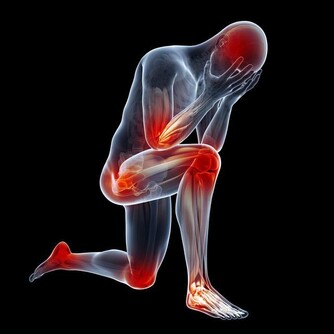

4、腰疼

身體裡面的尿酸如果堆積很多,腎臟就會出現非常嚴重的負擔,容易導致腎結石問題出現,腎臟出現問題就會影響到腰部的健康,容易出現疼痛感覺,情況嚴重的話還容易導致失眠症狀出現,所以一定要特別注意。